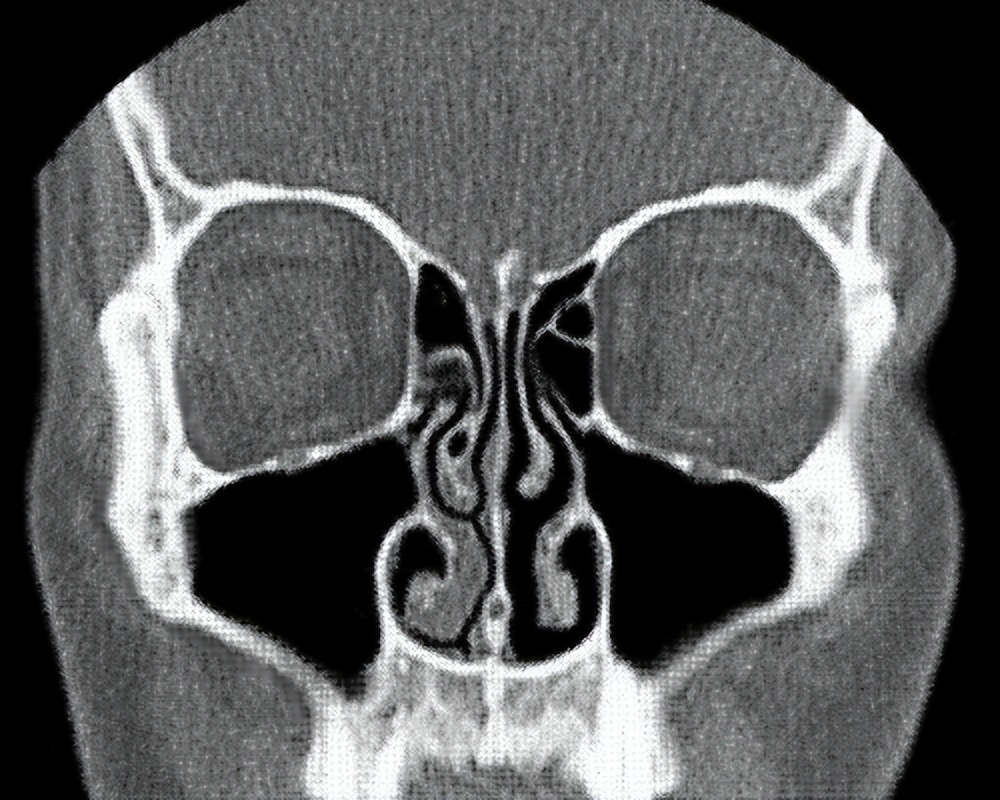

在正常状态下,我们的一个鼻孔处于主要的工作状态来进行呼吸,而另一个鼻孔的呼吸量很少,处于暂时的休息状态。过一段时间另外一只鼻孔开始工作,先前工作的鼻孔则进入休息状态。这种交替工作和休息的过程就叫做 鼻循环 。

也就是说,我们平时吸入和呼出的大部分气体只通过一个鼻孔进出,只有少部分气体会通过另一个鼻孔,因此两个鼻孔总是一侧通一侧相对不通。 事实上,无论是正常还是感冒的状态下,鼻循环都是一直存在的。

鼻循环的时间周期一般为2个小时以上,且随着年龄的增长,循环周期也会逐渐变长,最长的甚至会达到8个小时进行一次循环。我们体内的 植物性神经系统 负责交换两只鼻孔的角色,保证这一交替过程的顺利完成。